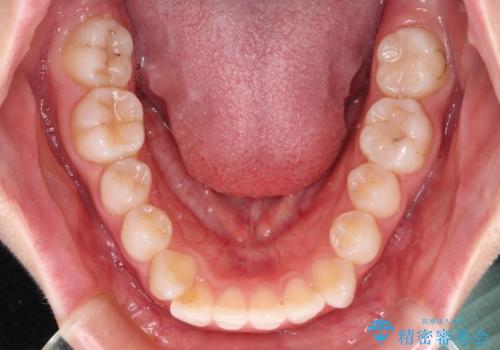

- 前歯の出っ歯と口元の閉じにくさを気にして来院された患者様です。

口元を積極的に引っ込めるために、上下左右の小臼歯4本を抜歯することとしました。

4本の歯を抜歯したことで、飛び出していた口元が引っ込み、横顔が大きく改善されました。